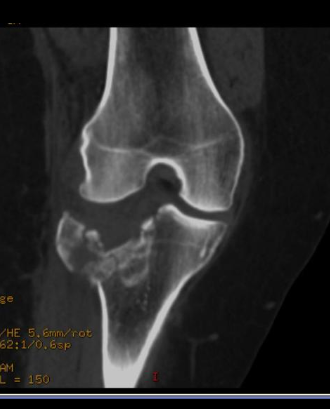

Osteoma Osteóide - A TC mostra o nidus radioluscente, cercado por reação esclerótica e , as vezes, pode mostrar um ponto esclerótico dentro do nidus.

Predomina 10 - 30 anos.

Nicho radiotransparente < 1cm circundado por reação esclerótica. Localização cortical / justacortical em ossos longos: femur proximal e tibia.

Clinica tipica: dor mais intensa a noite aliviada por AAS.

Quando nidus > 2cm = osteoblastoma. TC é a modalidade de escolha (RM pode não ver o nidus).